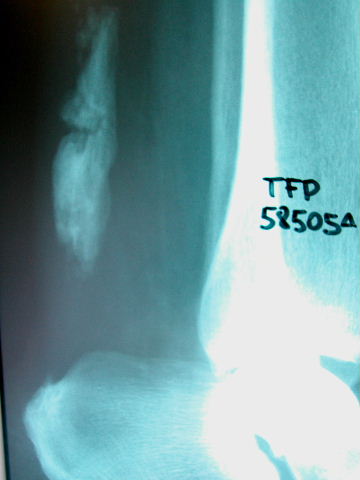

APR Fractura bimaleolar de tobillo